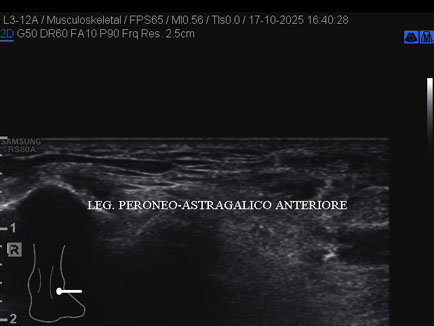

Ecografia del: 17/10/2025

Età Paziente: M

Commento all'esame: rottura del fascio antero-superiore del legamento fibulo-talare anteriore con integrità del fascio postero-inferiore in giovane calciatore.

Conclusioni: rottura del fascio antero-superiore del legamento fibulo-talare anteriore destro (tear of the anterosuperior bundle of the right anterior talofibular ligament).